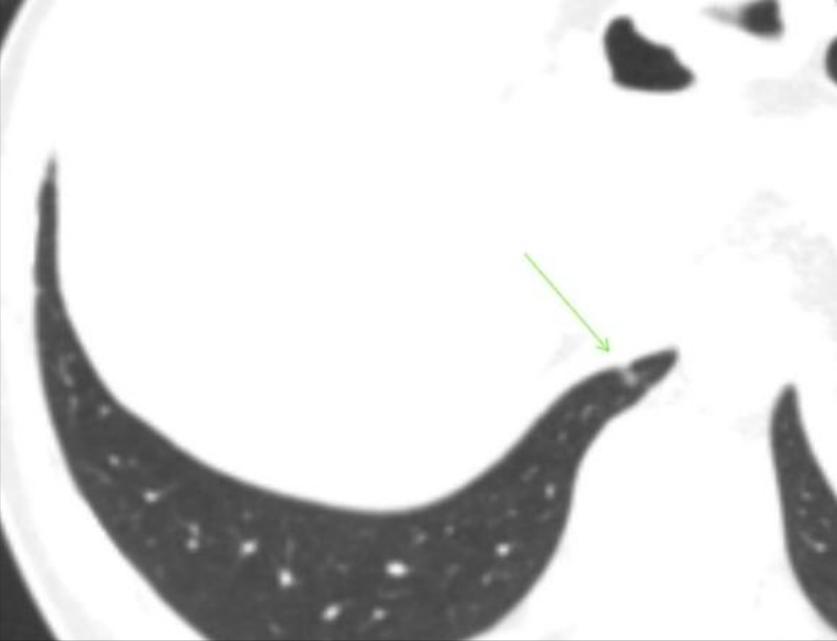

6月6日,我在本地三甲肿瘤医院复查薄层CT,报告显示:8mm混磨消了!只有一个上次就有的3mm的钙化灶,和一个新发现的2mm的结节,考虑增殖结节。

我不知道是不是可以祝贺自己了。现在还有一个右肺下叶后基底段结节考虑增殖结节,麻烦主任再帮我看看。